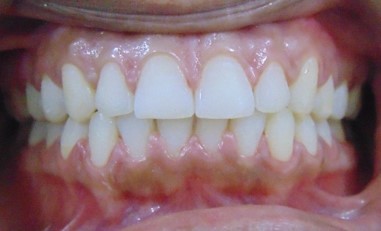

Divya Patil, 28Y, Duration - 6Months

Before

After

Image 1